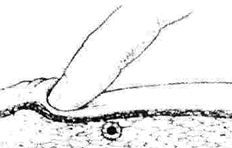

Рис. 105. Методика пальпации триггерной точки [230]

Диагностика проводится скользящей пальпацией поперечно направлению мышечных волокон. Пальпация облегчается, если исследуемую мышцу несколько растянуть, поскольку в заинтересованных волокнах порог вызывания миотатического рефлекса выше, чем в интактной мышечной ткани. Кожу над исследуемым участком можно смазать массажным маслом для снижения поверхностного трения.

Кинестетически ТТ определяется как гиперраздражимая область диаметром 1,5 - 3 мм, которая значительно менее выражена в нескольких миллиметрах от её границы (рис. 105). Механическое сдавление ТТ нередко способствует судорожному сокращению содержащего её мышечного волокна (локальный судорожный ответ) и часто вызывает несегментарные сосудистые, секреторные или пиломоторные вегетативные реакции. Иногда при выявлении ТТ больной реагирует болезненной гримасой или непроизвольным вздрагиванием («симптомом прыжка») [230, 180].